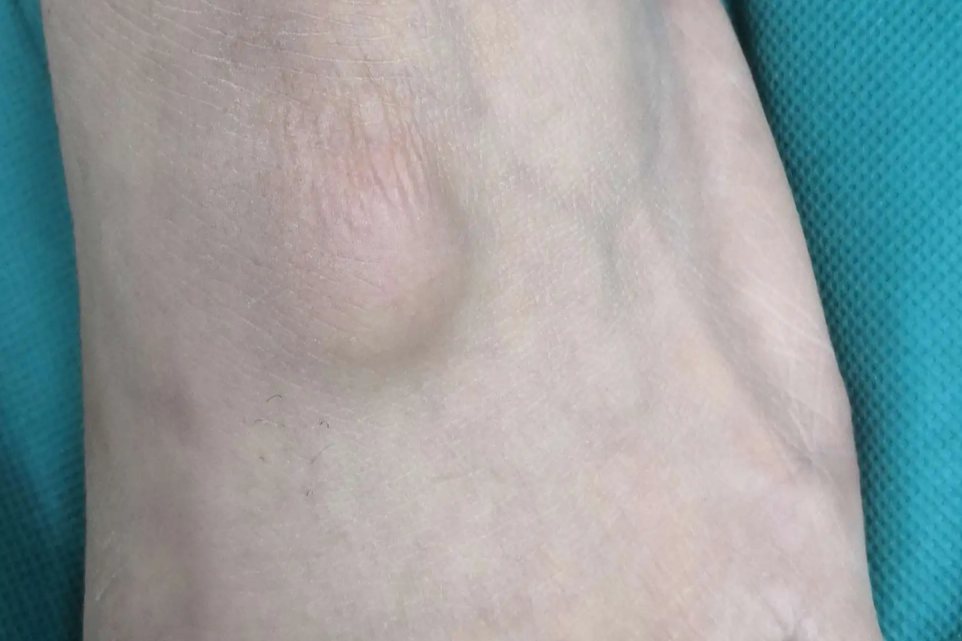

腱鞘囊肿

腱鞘囊肿好发于足背、腕背侧、肘膝关节附近的肌腱及腱膜处。临床表现为缓慢生长的局部圆形肿块,直径一般不超过2cm。光滑无粘连,基底相对较固定,质地软,无压迫神经时通常无明显疼痛。

少数腱鞘囊肿可自行消退,大部分会持续存在或增大,如影响关节功能需要进行治疗,包括针刺抽液注射糖皮质激素,以及手术切除囊肿等治疗。